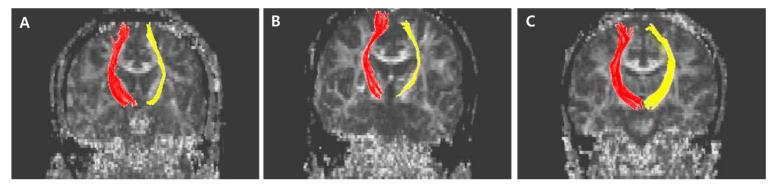

A stroke may be followed by central post-stroke pain (CPSP), which is characterized by chronic neuropathic pain. The exact mechanism has not yet been fully uncovered. We investigated alterations in the white matters in patients with CPSP, compared with stroke patients without CPSP and normal controls. Our retrospective cross-sectional, case-control study participants were assigned to three groups: CPSP (stroke patients with CPSP ( = 17)); stroke control (stroke patients without CPSP ( = 26)); and normal control (normal subjects ( = 34)). The investigation of white matter for CPSP was focused on the values of fiber numbers (FN) and fractional anisotrophy (FA) for spinothalamic tract (STT), anterior thalamic radiation (ATR), superior thalamic radiation (STR) and posterior thalamic radiation (PTR), and corticospinal tract (CST) was measured. The FA for the STT and STR of the CPSP group were lower than those for the stroke control and normal control groups. The FA of CST and ATR did not differ between the CPSP and stroke groups, but both differed from the normal control. The FA of PTR in the stroke control group differed from the normal control group, but not from the CPSP group. The FN of CST, STT, ATR, and STR for the CPSP and stroke control groups did not differ from each other, but both differed from those of normal controls. FN of PTR did not differ between the CPSP and normal control groups. The alterations in the spinothalamic tract and superior thalamic radiation after stroke would play a role in the pathogenesis of CPSP.

中风后可能会出现中枢性中风后疼痛(CPSP),其特征为慢性神经性疼痛。确切机制尚未完全揭示。我们对CPSP患者的白质变化进行了研究,并与无CPSP的中风患者及正常对照进行比较。我们的回顾性横断面病例对照研究参与者被分为三组:CPSP组(患有CPSP的中风患者( = 17));中风对照组(无CPSP的中风患者( = 26));以及正常对照组(正常受试者( = 34))。对CPSP白质的研究重点在于脊髓丘脑束(STT)、丘脑前辐射(ATR)、丘脑上辐射(STR)和丘脑后辐射(PTR)的纤维数量(FN)值和分数各向异性(FA),并测量了皮质脊髓束(CST)。CPSP组的STT和STR的FA低于中风对照组和正常对照组。CPSP组和中风组之间CST和ATR的FA没有差异,但两者均与正常对照组不同。中风对照组中PTR的FA与正常对照组不同,但与CPSP组无差异。CPSP组和中风对照组的CST、STT、ATR和STR的FN彼此无差异,但两者均与正常对照组不同。CPSP组和正常对照组之间PTR的FN没有差异。中风后脊髓丘脑束和丘脑上辐射的变化在CPSP的发病机制中起作用。